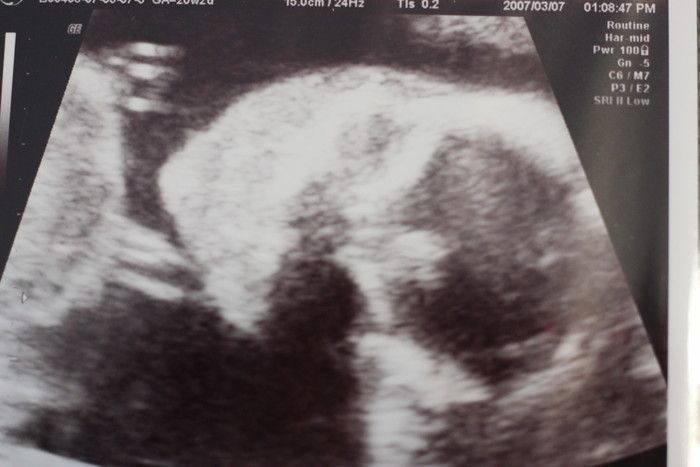

たかこさんの妊娠20週目のエコー写真 ちょっとホラー並みのエコー写真でコンニチワ

エコー写真ではいつも背中を向けていた胎児が、ついにこっちを向きました。すると、ちょっとしたホラーのような写真に…。写真下の絵は、先生の手書きの説明です。この頃になると、全長を測るのではなく、大腿骨長(太ももの骨の長さ)を測り、大きさの目安にすると先生に説明されました。この時に男の子のシンボルがしっかり映り、性別もほぼ確定しました。つわりもようやくなくなりました。